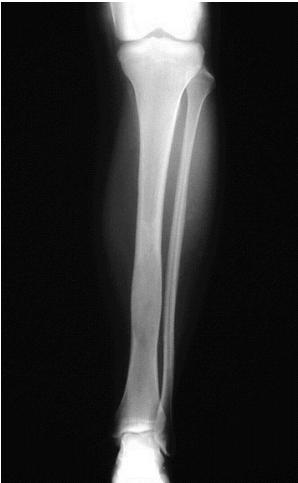

Non-ossifying Fibroma

site: Diaphyseal, metaphysal size: partial matrix: Mixed - Narrow zone of transition, well defined, syndosmosis soft tissue involvement: No tissue involvement